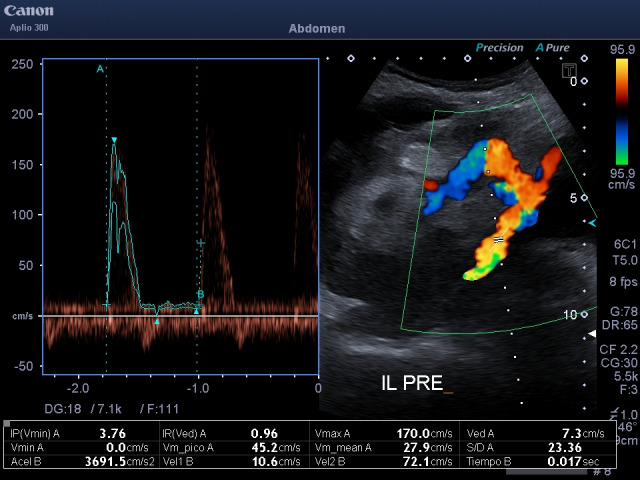

Abstract Image